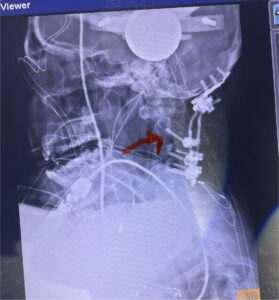

Fig 8: Intraoperative photograph demonstrating occipital-cervical construct and C1 laminectomy (blue dot). Note the 3 screws in the midline keel (blue arrow)

Cervical x-rays revealed a significantly increased atlanto-axial interval (Fig. 5) On review of her imaging studies it was noted that the right C2 isthmus was very thinned by the vertebral foramen (Figs 6a, b, and c) which would make an attempt at placing a C2 pars screw dangerous. A decision was made to perform an occipital-cervical fusion because only possible unilateral fixation and an extensive C1 laminectomy to be performed eliminating a fixation point if a more traditional C1-C2 was performed. Even if C1 lateral mass screws were able to be placed one could only perform a unilateral screw construct fixation to C2. We performed an occipital cervical fusion down to C4 to get enough inferior fixation and C1 laminectomy. The decompression went well. We placed a left unilateral pars screw and bilateral C3 and C4 lateral mass screws. We placed three 12 mm screws in the midline keel (Fig. 7). Postoperatively the patient had all around improvement in her symptoms and did not qualify for rehab. Her post op films at 6 weeks (Fig. 8)